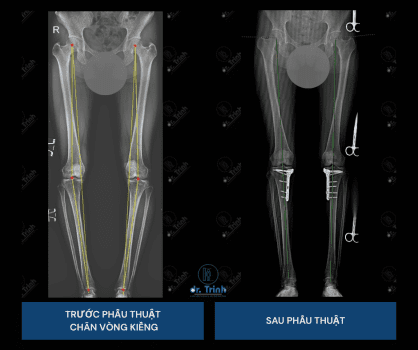

Chân vòng kiềng là tình trạng hai chân bị cong ra ngoài, khiến đầu gối không chạm nhau khi đứng thẳng. Dù không nguy hiểm ngay lập tức, tình trạng này dễ gây mất thẩm mỹ, mất cân bằng dáng đi và có thể dẫn đến thoái hóa khớp gối sớm nếu không can thiệp.

Trong nhiều trường hợp, phẫu thuật chân vòng kiềng là giải pháp hiệu quả để chỉnh trục chân, giúp dáng đi tự nhiên và tăng sự tự tin.